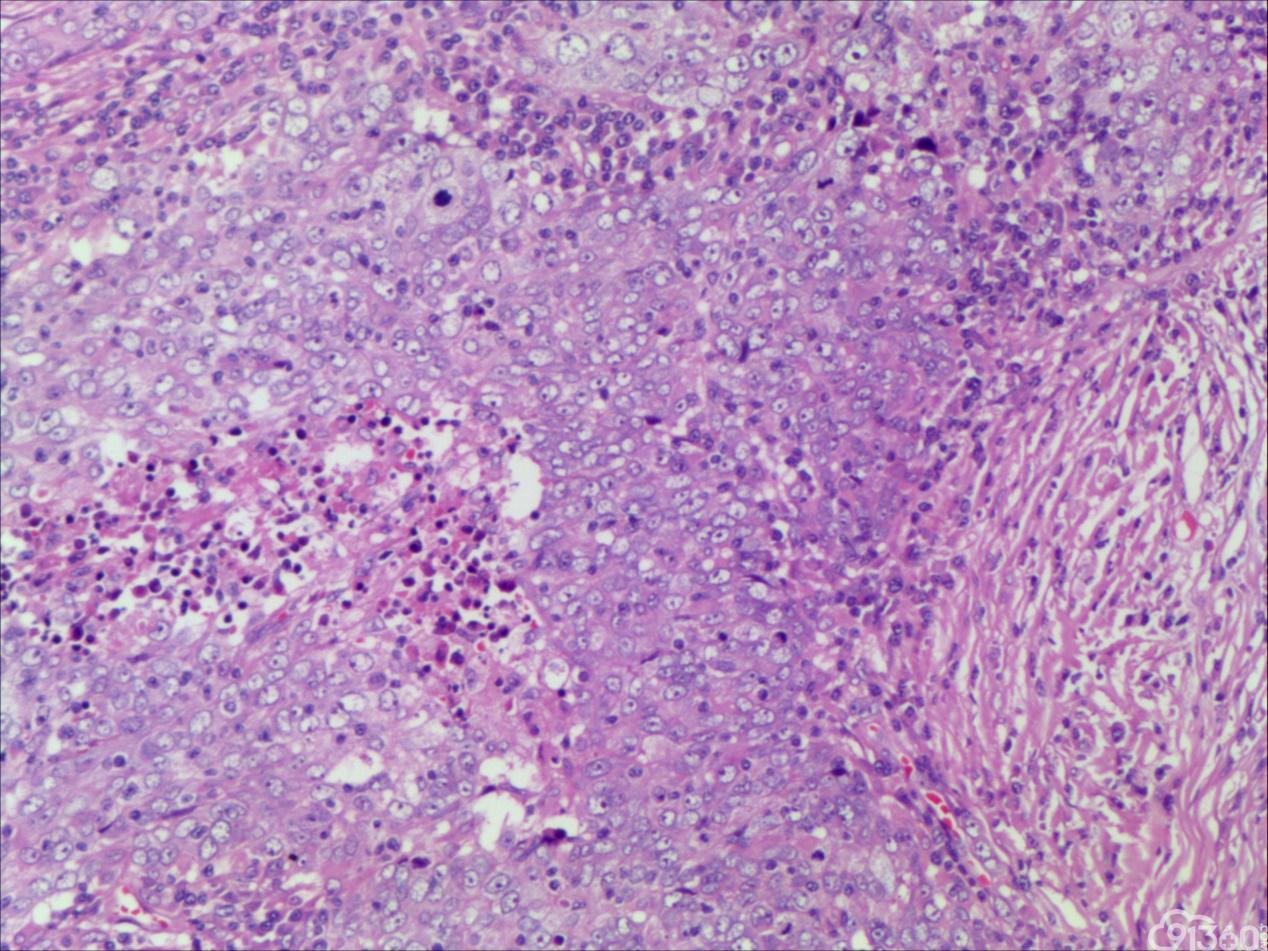

具有髓样癌特征的乳腺癌病理